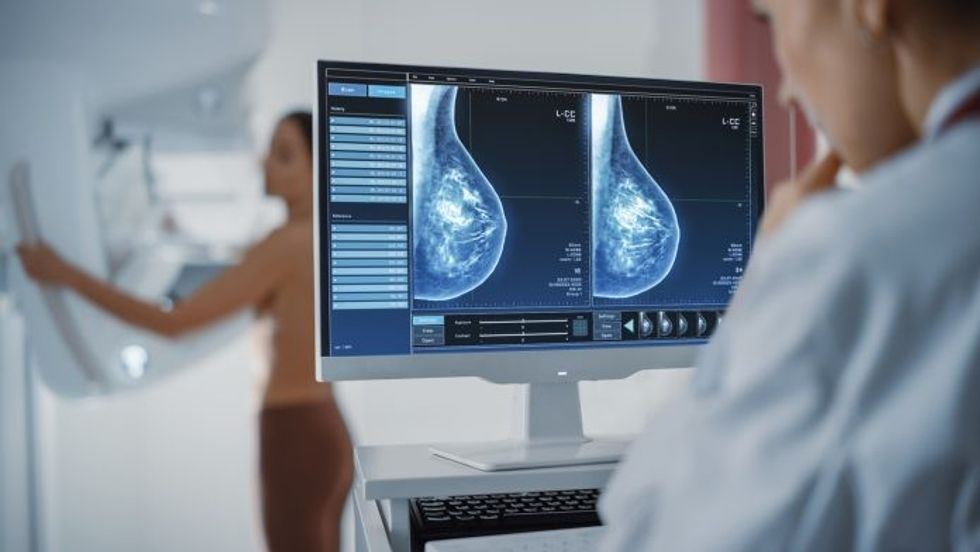

Përdorimi i inteligjencës artificiale në depistimin e kancerit të gjirit është i sigurt dhe pothuajse mund të përgjysmojë ngarkesën e punës së radiologëve, sipas studimit më gjithëpërfshirës në botë të këtij lloji

Rezultatet paraprake nga një studim i madh sugjerojnë se ekzaminimi i inteligjencës artificiale është po aq i mirë sa dy radiologë që punojnë së bashku, nuk rrit rezultatet false dhe pothuajse përgjysmon ngarkesën e punës.

Rezultatet e analizës së përkohshme të studimit, i cili përfshiu më shumë se 80,000 gra, u botuan në revistën Lancet Oncology.